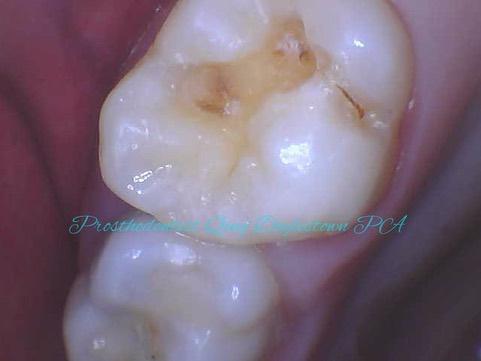

Figure 1 shows some shadow on the intact tooth surfaces, until it is opened up to find out how much decay was underneath.